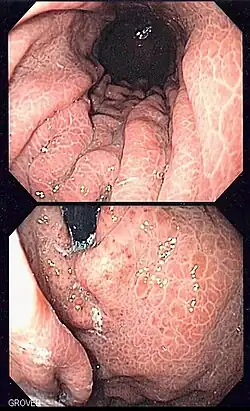

Unter einer Gastropathia hypertensiva (hypertensive Gastropathie) versteht man die Erweiterung von Venen der Magenschleimhaut durch den Rückstau venösen Blutes aufgrund eines erhöhten Blutdruckes im portovenösen Stromgebiet. Durch die Erweiterung kann es analog der Ösophagusvarizen zu einer akuten intestinalen Blutung mit potenziell letalem Ausgang kommen. 10 % der Blutungen durch portale Hypertension haben eine hypertensive Gastropathie als Ursache.

Als Wassermelonenmagen werden rötlich-streifig aussehende (dem Muster auf der Schale der Wassermelone ähnelnde) Angiektasien des Magens mit zum Teil erheblicher Blutungsgefahr bezeichnet; häufig treten sie im Rahmen einer hypertensiven Gastropathie oder bei systemischer Sklerodermie auf.